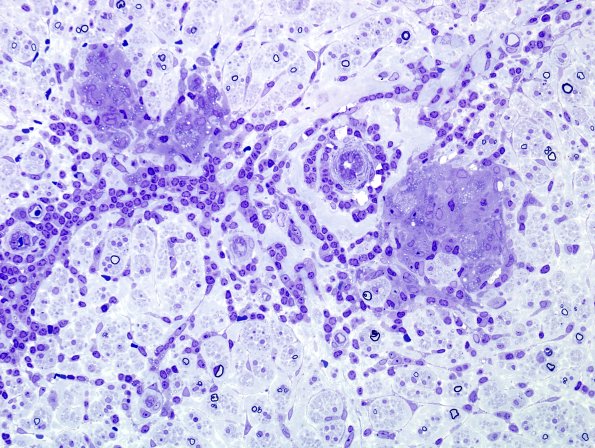

Washington University Experience | PERIPHERAL NEUROPATHY | 10 INFECTION | 5 Leprosy - Other | 1B3B Leprosy, tuberculoid (Case 1) Plastic 7

Patchy collections of epithelioid histiocytes form small granulomas. There are small residual myelinated axons. (plastic sections)